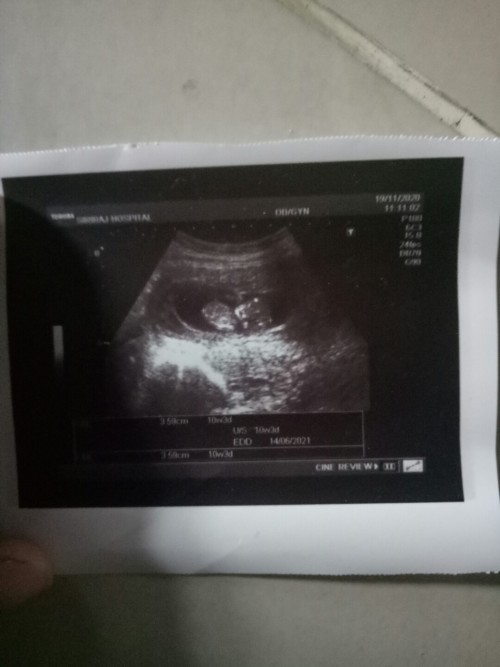

8มิ.ย64จ้า 10วีค